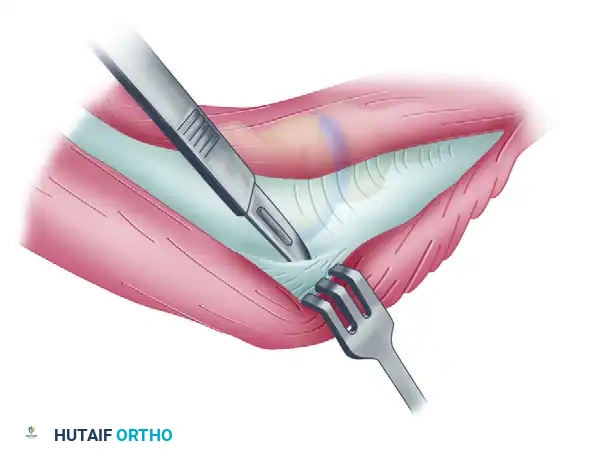

Deep Dissection and Anterior Capsulectomy

The goal of the anterior dissection is to safely separate the neurovascular structures from the anterior capsule before performing the capsulectomy.

- Carefully elevate the brachialis muscle belly off the anterior joint capsule. This must be done meticulously, as the brachialis serves as a protective barrier for the brachial artery and the median nerve.

- Place blunt retractors (such as right-angle or Hohmann retractors) deep to the brachioradialis and brachialis muscles. This maneuver safely retracts the anterior neurovascular bundle and exposes the underlying, thickened anterior joint capsule.

- Perform a comprehensive anterior capsulectomy, proceeding systematically from lateral to medial.

- Critical Step: Identify and preserve the lateral collateral ligament (LCL) complex, specifically the lateral ulnar collateral ligament (LUCL). The capsulectomy must stay strictly anterior to the LCL origin on the lateral epicondyle to prevent iatrogenic posterolateral rotatory instability (PLRI).

Surgical Warning: When extending the anterior capsulectomy medially, maintain the dissection strictly within the capsular plane. Straying anteriorly risks injury to the median nerve and brachial artery, while straying too far medially and posteriorly risks injury to the ulnar nerve.